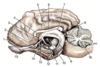

MRI ANATOMY QUIZ! CAN YOU NAIL IT??

Label the diagram (MAJOR STRUCTURES ONLY!)